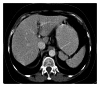

Spleen can have a wide range of anomalies including its shape, location, number, and size. Although most of these anomalies are congenital, there are also acquired types. Congenital anomalies affecting the shape of spleen are lobulations, notches, and clefts; the fusion and location anomalies of spleen are accessory spleen, splenopancreatic fusion, and wandering spleen; polysplenia can be associated with a syndrome. Splenosis and small spleen are acquired anomalies which are caused by trauma and sickle cell disease, respectively. These anomalies can be detected easily by using different imaging modalities including ultrasonography, computed tomography, magnetic resonance imaging, and also Tc-99m scintigraphy. In this pictorial essay, we review the imaging findings of these anomalies which can cause diagnostic pitfalls and be interpreted as pathologic processes.